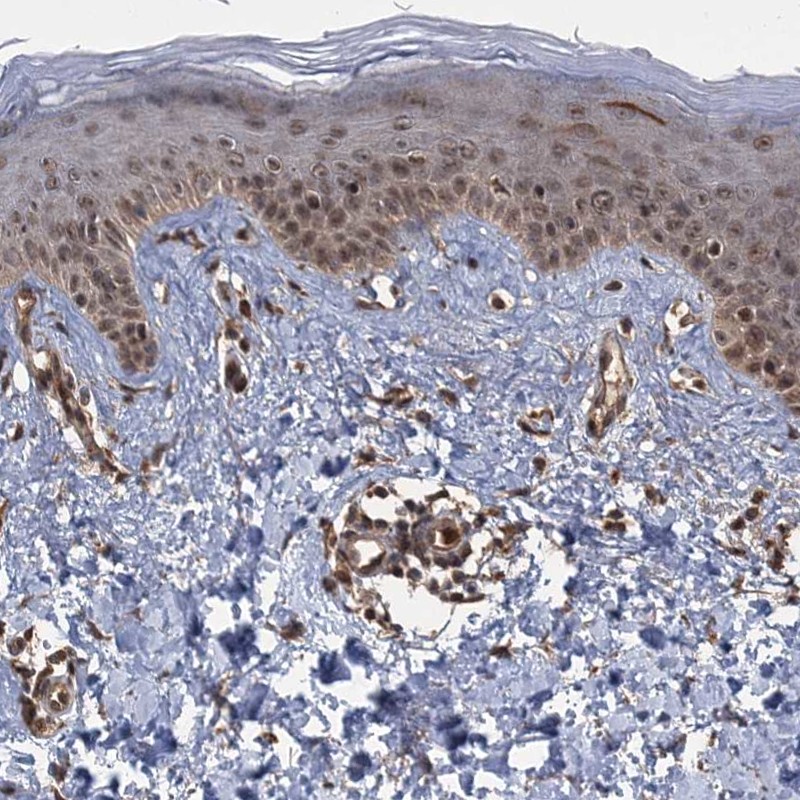

Immunohistochemical staining of human skin shows moderate nuclear positivity in keratinocytes.